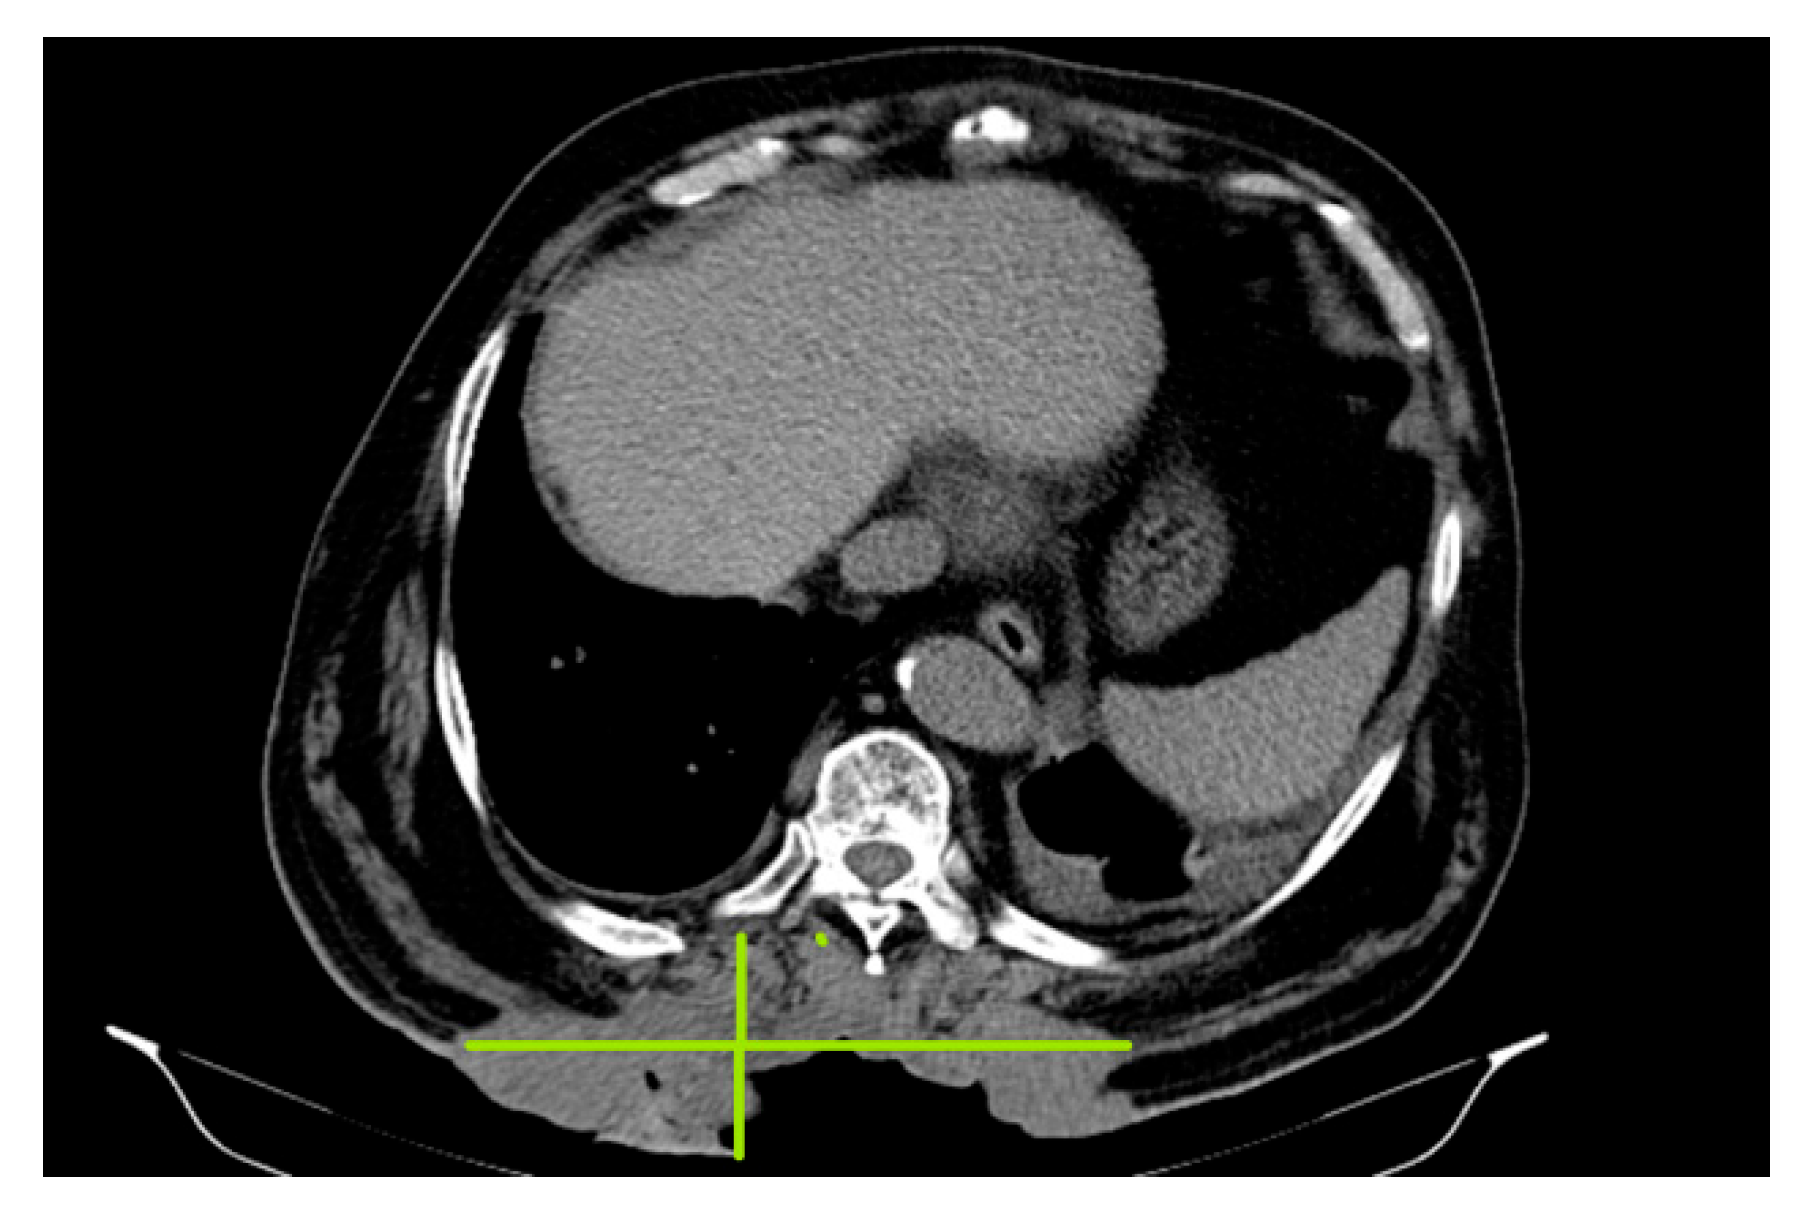

In October 2018, a thoracic, abdominal-pelvic CT scan was performed with contrast material. The imaging aspect was aggravated from the previous examination (July 2018) by the significant dimensional progression of the mass, with the malignant tumor CT aspect centered at the level of the muscular soft parts corresponding to the posterior thoracic lumbar region (level T7-D2), currently with invasion of the tegument, subcutaneous fat, and embedding of the spinal processes of the T9–T11 vertebral bodies, axial diameters (197/46 mm), and cranio-caudal diameter (212 mm–11/46 anterior); the presence of central necrotic areas at the level of the tumor mass was described (Figure 2).

Figure 2. :Malignant tumor CT aspect centered at the level of the muscular soft parts corresponding to the posterior thoracic lumbar region (level T7- D2), currently with invasion of the tegument, subcutaneous fat and embedding of the spinal processes.